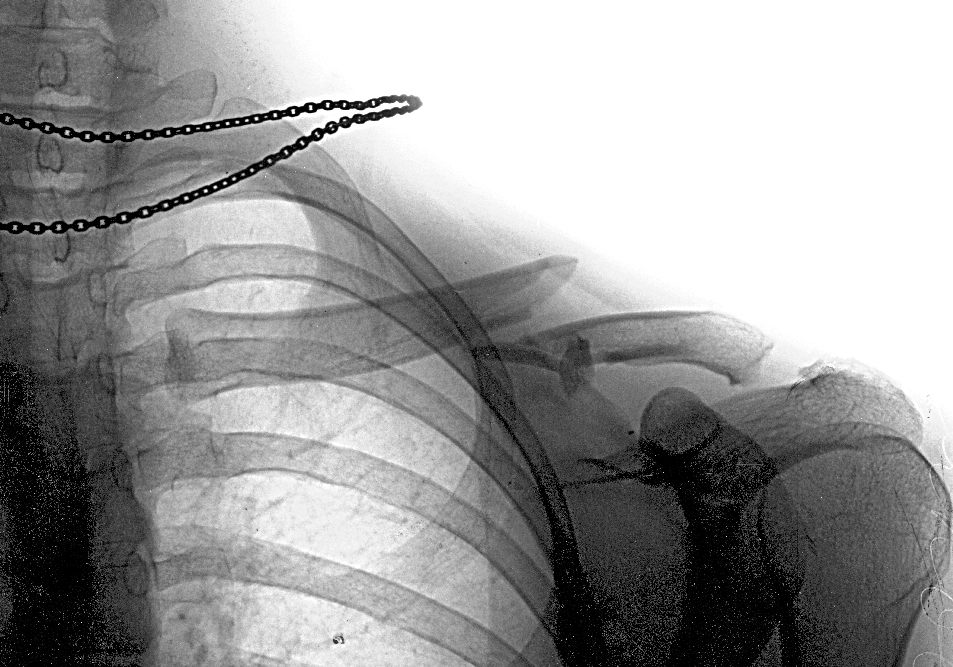

У меня было так:

Вправили в травмпункте Склифа, стало вот так: